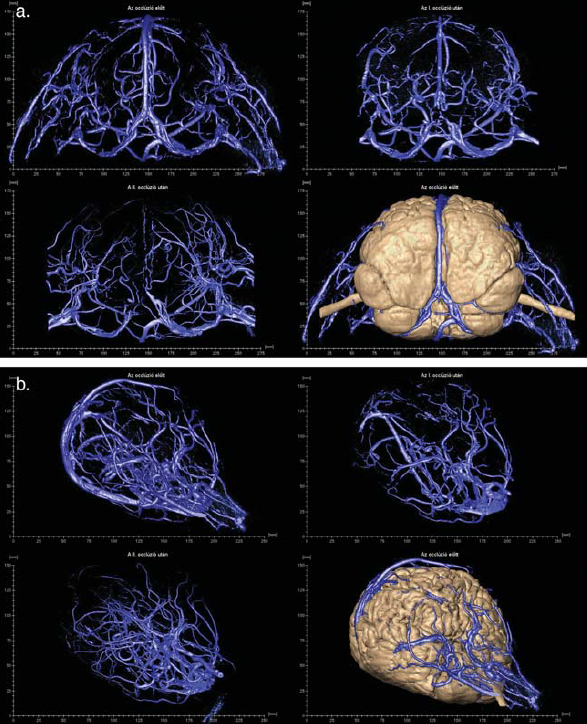

3/a,b. ábra.

Az agyak vénás hálózatának 3D rekonstrukciója az okklúzió egyes fázisaiban.

Az occlusio után sem az altatás idején, sem az ébredés után, sem pedig a következő időszakban nem kivánatos esemény nem történt. Tehát az ikrek sem agyi oedema, sem bármely neurologiai deficit jelét nem mutatták. Az egyik gyermeknél (Rukaya) kialakult magas láztól eltekintve, a beavatkozás nem okozott iatrogén ártalmat. A később elvégzett MRI angiografia kimutatta az embolizáló anyagot a lezárt sinusban (3/a,b. ábra).

Itt kell megemlítenünk az eddig, sziámi ikreknél még ebben a részletességben nem alkalmazott módszert, a 3D modellezést, amelynek segítségével további, alapvetően fontos információhoz jutottak részben az első fázis sikere szempontjából, de később is. A magyar team tagja lett Czeibert Kálmán, aki a számítógépes grafika és az ennek alapján készített 3D modellek szakembere volt. Ő eredeti végzettsége szerint állatorvos, aki neuroanatómiai témájú PhD-munkája során ismerkedett meg ezzel a technikával. Jelen esetben az ismételt képalkotó eljárások felvételei alapján szerkesztett modelljeivel plasztikusan tudta ábrázolni az ikrek agyát és annak ereit, több síkból lehetővé téve tanulmányozásukat, ezáltal a műtét begyakorlását. Az ő segítségével derült ki, hogy Hudák István beavatkozása után még mindig van egy olyan nagyobb nyitott véna a két agy között, amelyet szintén el kell zárni. Őt tarthatjuk e történet negyedik főszereplőjénnek, vagyis kulcsemberének, aki nemcsak új módszert hozott be a vizsgálóeljárások közé, hanem azért is, mert átlagon felüli tehetségével, eredeti meglátásaival, jelentős része volt a projekt sikerében. Ez volt az első eset, hogy MRI és CT angiográfiás felvételekből speciális programokkal felfedezte és pontosan lokalizálta, valamint modellen a valóságban is megjelenítette azt az intracerebrális vénás sinust és ágrendszerét, amely az első embolizáció után nyílt meg, s amit a korábbi vizsgálatok nem mutattak, de nem is mutathattak ki, mivel elképzelhető, hogy az első beavatkozás idején még nem is léteztek (vagy nem voltak láthatóvá tehetőek a képalkotó eljárásokkal).

A februári beavatkozás után 6 hónappal elvégzett kontroll vizsgálat szerint ugyanis a megváltozott áramlási viszonyok miatt új véna, egy belső vénás sinus alakult ki a két összefekvő agyfelszín között, amelyet az orvosok intracerebralis felső sagittalis sinusnak neveztek el. Ez a lelet valószínűleg igen súlyos, esetleg fatális, későbbi intraoperatív vérzéses szövődmény lehetőségét előzte meg. Czeibert Kálmán új módszerével, kifinomul agyi struktúrák különleges megjelenítésével és szerepüknek hangsúlyozásával tehát valószínűleg megmentette az ikrek életét. A második (kiegészítő) occlusiot kizárólag emiatt határozták el és ennek céljából Hudák István és Csókay András ismét Dhakába utaztak és 2018 augusztus 19.-én sikerrel megtörtént a második embolizáció is (4. ábra).